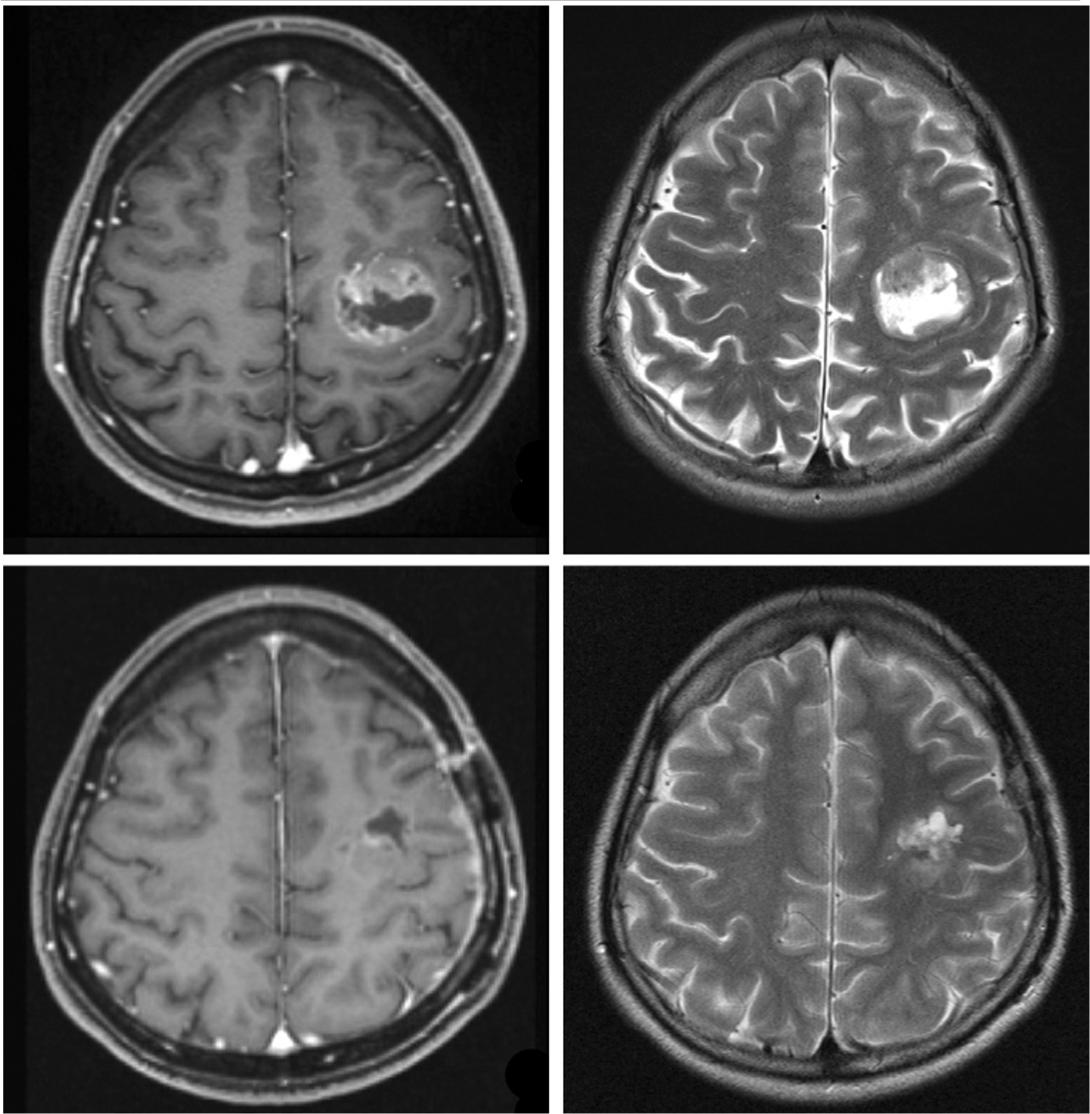

Initial symptom was gradually deteriorating right hand monoparesis of four months duration. Radiological examination showed a round heterogeneous mass located at the ventral side of precentral gyrus in the left frontal lobe (Figure 1, upper). Intraoperative motor evoked potential and somatosensory evoked potential mapping successfully indicated the central sulcus and precentral gyrus in the operative field. Internal decompression of the tumor was performed through minimum corticotomy to avoid damage of the eloquent areas of the brain. Histopathological diagnosis was anaplastic ependymoma and 80% of the enhanced lesion was removed (Figure 1, lower). Adjuvant conventional radiotherapy was added. She recovered motor function in the right upper extremity. Two years after the initial surgery, she presented with a progressively worsening right upper extremity (U/E) paresis, manual muscle testing (MMT) 3. Neuroimaging investigations confirmed tumor regrowth. A second surgery was scheduled. Prior to the second surgical treatment, functional magnetic resonance imaging (fMRI) and tractography confirmed the right motor function to be located in the left precentral gyrus and connected to pyramidal tract (Figure 2). Internal decompression was performed again with the aim of preserving and recovering her left U/E function. Histopathological diagnosis was as same as the initial surgery, but MIB-1 labeling index increased. After the second surgery, rapid local regrowth of the tumor was observed. Two further surgeries for internal tumour decompression and Ommaya reservoir placement for evacuation of fluid in the tumour removal cavity were necessary in one year. Temozolomide, procarbazine and interferon-beta were not effective for tumor control.

Magnetic resonance imaging (MRI) before initial operation showing the round ringed enhanced lesion in the left motor area without massive perifocal edema (upper). Postoperative MRI showing that the small remnant tumor left at the parietal side of removal cavity (lower).